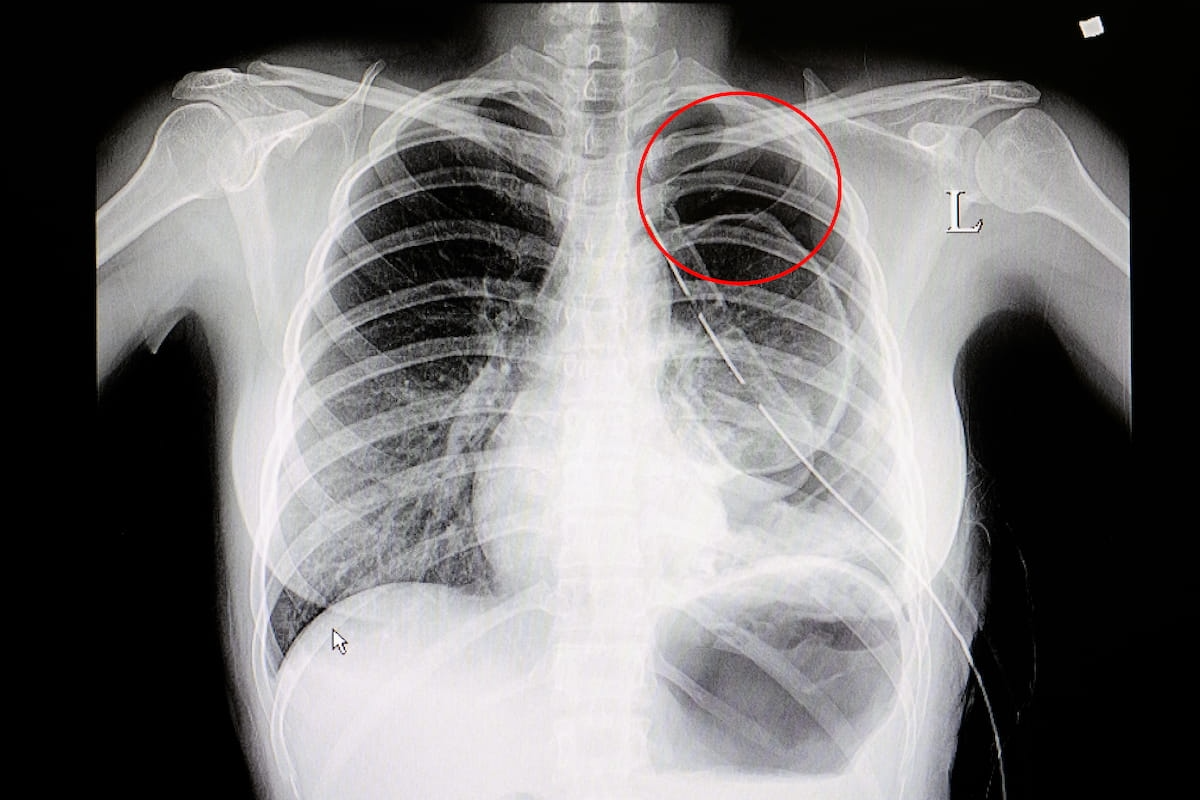

Artificial intelligence (AI) assessments of chest X-rays identified 28 percent of a 17,000 plus cohort of never-smokers as being at high-risk for lung cancer, according to research to be presented at the annual Radiological Society of North America (RSNA) conference next week.